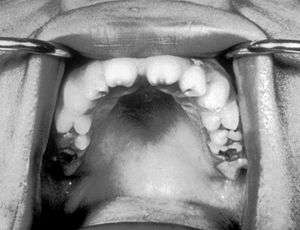

Notched incisors known as Hutchinson's teeth which are characteristic of congenital syphilis

A frequently-found group of symptoms is Hutchinson's triad, which consists of Hutchinson's teeth (notched incisors), keratitis and deafness and occurs in 63% of cases.[4]